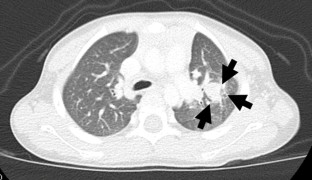

Navigation surgery using ICG was performed for primary liver tumors in 4 cases, and the timing of ICG injection was 90.5 ± 33.7 h before the operation. All tumors exhibited intense fluorescence from the liver surface. ICG navigation for the primary liver tumor was useful for detecting the residual tumor at the stump and invasion to the diaphragm during surgery. Six lung surgeries using ICG navigation were performed. The timing of ICG injection was 21.8 ± 3.4 h before the operation. The size of the metastatic tumor was 7.4 ± 4.1 mm (1.2–15 mm). Of 11 metastatic tumors detected by computed tomography (CT), 10—including the smallest tumor (1.2 mm)—were able to be detected by ICG from the lung surface. The depth of the 10 ICG-positive tumors from the lung surface was 0.9 ± 1.9 mm (0–6 mm), and the depth of the single ICG-negative tumor was 12 mm. One lesion not detected by CT showed ICG false positivity.